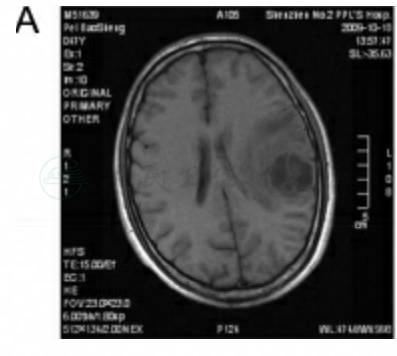

术后病理:胶质母细胞瘤,部分为小胶质母细胞(图4)。

图3

图4 病例2病理切片